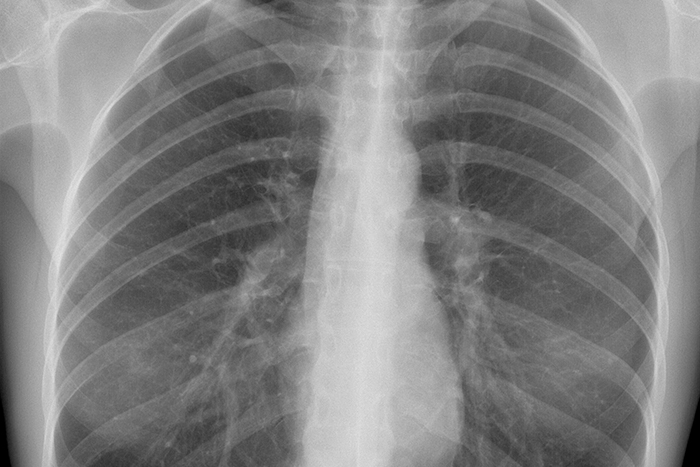

Toutes les parties du corps humain, y compris le thorax, le bassin, l'abdomen, les mains, les pieds et la tête de l'adulte. Temps d'installation inférieur à 1 minute

Image radiographique de qualité supérieure

70kV : meilleure pénétration de l'image. Amélioration de l'identification des os. 6mA : Réduction du temps d'irradiation nécessaire. Réduit le flou de mouvement. Spot focal de 0,4 mm > Haute résolution